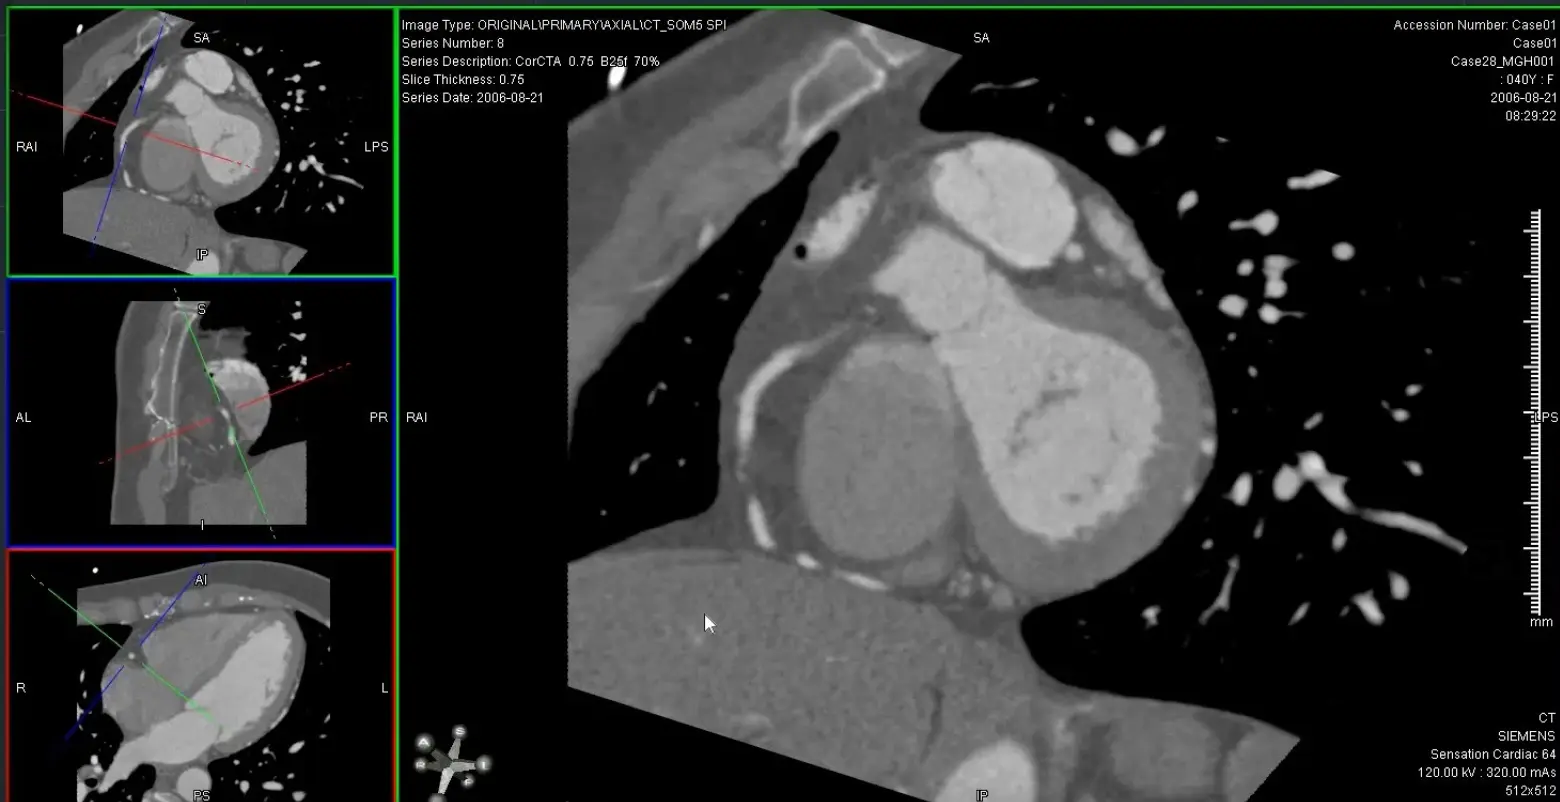

- Generate orthogonal views of coronary arteries using MPR (e.g. 0.5 mm thickness) to be able to evaluate luminal narrowing

- → Align 2 view through the long axis

- → Then double click on the remaining plane to see the SAX and evaluate for luminal stenosis

- Use the SAX images to measure 📐 luminal stenosis

- Reset your view and line up 2 orthogonal views → visualize SAX view